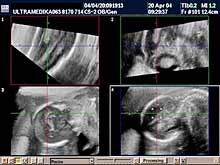

B) II trimestar trudnoće

od 16 do 24

nedelje gestacije

(4 - 6 meseca):

Indikacije za ultrazvučni pregled:

- GENETSKI SONOGRAM

(15-16 nedelja gestacije - 4. mesec):

Otkrivanje ultrazvučnih (soft) markera (markeri koji nisu prisutni u

i trimestru

trudnoće) na postojanje hromozomskih anomalija. Ovaj ultrazvučni

skrining se radi 15- 16 nedelji gestacije u ranom II trimestru

trudnoće. Sam otkriva oko 91% plodova sa aneuploidijama.

Napomena: Nezavisno od ultrazvučnog skrininga, same biohemiske analize

krvi trudnice do 35 godina starosti trudnice otkrivaju ispod 50%

trizomija. Optimalno je uraditi biohemiski skrining iz krvi trudnice

proverom 4 substance.

- SKRINING NA ANATOMSKE ANOMALIJE:

- registrovanje i procena

ultrazvučnih markera koji ukazuju na postojanje adekvatno završenog

formiranja organa ploda (embriogeneze).

Većina plodova sa poremećenom embriogenezom i postojanjem anatomskih anomalija (mozga, kičme, srca,

pluća, organa stomaka, prednjeg trbušnog zida,udova itd) se može

otkriti jedino ultrazvukom.

Napomena: a)

Provera plodove vode i druge invazivne metode ne registruju anatomske

anomalije. b)

Radi adekvatne procene postojanja anatomskih anomalija pored Broadband

2D se koristi i 3D Sono CT i 3D CPA organskih sistema dostupnih

pregledu. 3D mekih tkiva lica je sastavni deo ultrazvučnog pregleda u

ovoj gestacionoj starosti. c)

Dopuna SKRININGA NA ANATOMSKE ANOMALIJE od

18-24. nedelje je

obavezan deo u otkrivanju urođenih anomalija ploda.

- Određivanje tačnog termina za primenu amniocenteze.

(15-16. nedelje gestacije)

- Definitivna procena posteljične cirkulacije pre odluke o primeni

terapije (Upotreba Braodband CD).

- Dopuna skrininga na anatomske anomalije ploda od 18-24. nedelje gestacije.

- 3D Sono CT SRCA PLODA (fetalna ehokardiografija) Prostorno, vremenska

korelacija ultrazvučnih markera prikazana multiplanarno predstavlja

dopunsku metodu u otkrivanju urođenih srčanih anomalija.

Napomena:

a)

Urođene srčane mane su 6 puta češće od hromozomskih anomalija i

njihova težina često zahteva prekid trudnoće. b)

Ovaj pregled je posebno registrovan za trudnoće koje su prethodno

imale plod sa srčanom manom ili kada u okviru standardnog pregleda

nisu dobijene sve validne ultrazvučne informacije radi pouzdanog

isključenja njihovog postojanja.

Mada je prva procena anatomije srca obavezna u I trimestru trudnoće,

konačna procena se mora završiti od 16 do kraja 24 nedelje gestacije

(6 meseci). Nakon toga procena osnovne anatomije je otežana i

rezervisana je za procenu hemodinamike srca!

- Procena dužine grlića i otvaranja unutrašnjeg ušća, kao i položaja

posteljice u odnosu na unutrašnje učće, je jedino moguća

endovaginalnom sondom. Na osnovu ovog pregleda se postavlja indikacija

za podvezivanje materice i način porođaja.

Endovaginalnu procena grlića i indikacija za serklaž je

obavezna do 22. nedelje gestacije, retko kasnije!

- Pregled organa trudnice